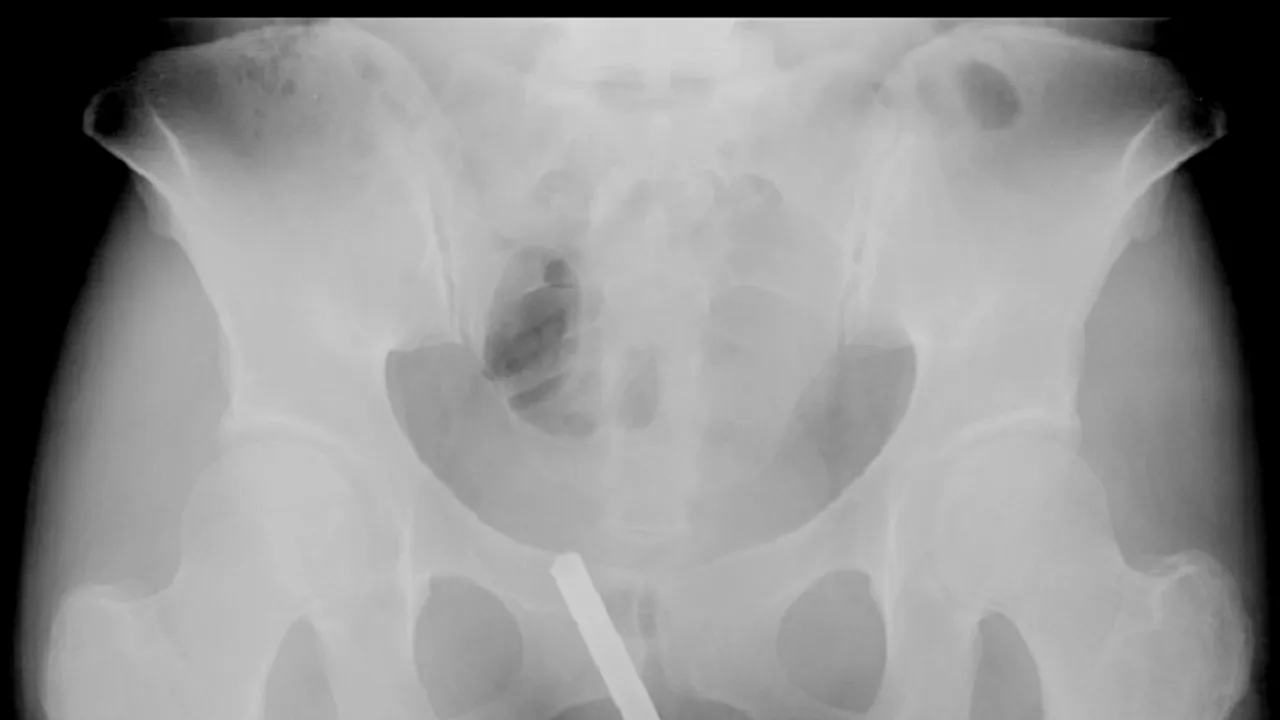

O femeie în vârstă de 28 de ani a fost arestată în Statele Unite ale Americii după ce polițiștii au descoperit că aceasta ascunsese un revolver, trei gloanțe și un cartuș folosit în vagin, informează The Sun.

După percheziție, aceștia au găsit și o punguța cu metamfetamină ascunsă în fundul femeii.